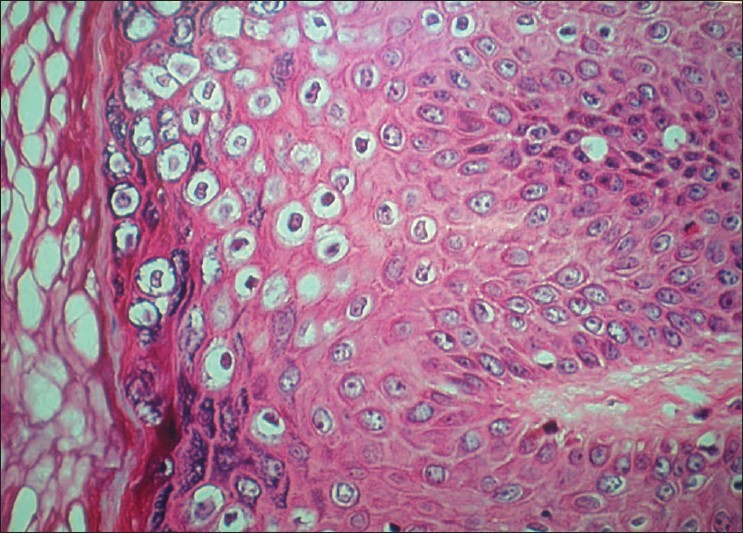

What is this a histology image of?

What other feature would be seen on histology which cannot be seen here (a feature of the epidermis)?

Viral warts

Papillomatosis